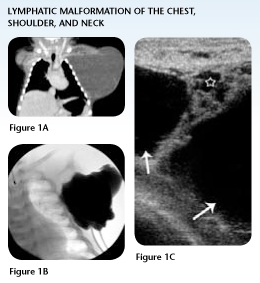

Case Study 1: Lymphatic Malformation of the Neck, Shoulder and Chest

In the first few hours of life, Hayden underwent a CT scan that clearly illustrated for the pediatric surgeon in Kentucky the extent of the mass, previously seen on a prenatal ultrasound.

The mass involved the left neck, shoulder and the entire length of the left chest wall. Surgical mapping indicated extensive surgical removal involving major nerves and vital structures, resulting in an up to 50 percent chance of recurrence.